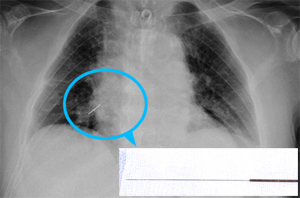

4월 초 침을 맞았다는 노 전 대통령은 18일 발생한 흉통으로 서울대병원에 입원했다.

서울대병원은 진료 이후 "한방에서 사용하는 손잡이 부분 2cm를 포함, 전체 길이 7cm의 금속성 침이 발견됐다"고 언급했다.